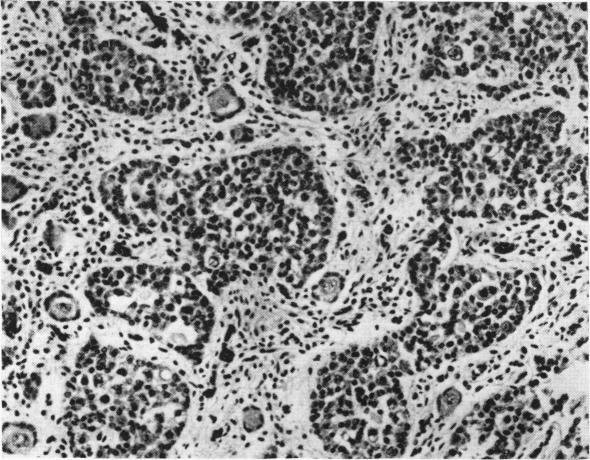

E (16-18) trisomy syndrome: analysis of 13 cases.

Arch Dis Child. 1965 Dec;40(214):600-11. doi: 10.1136/adc.40.214.600.